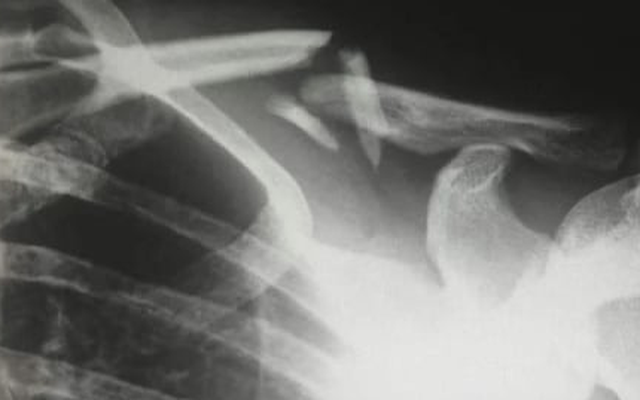

Việc lạm dụng kem chống nắng bất cứ khi nào đi ra ngoài khiến một người phụ nữ bị thiếu hụt vitamin D, dẫn đến tình trạng chỉ nằm trên giường cũng gãy xương.

Các bác sĩ tại Bệnh viện Y học cổ truyền XinDu, Thành Đô, Trung Quốc vừa báo cáo về trường hợp bất thường của một bệnh nhân tại địa phương. Người phụ nữ giấu tên, 48 tuổi bị gãy xương chỉ vì nằm lăn lộn trên giường.

Theo Tiến sĩ Long Shuang, các xét nghiệm được thực hiện tại bệnh viện cho thấy nồng độ vitamin D trong cơ thể của người phụ nữ cực kỳ thấp. Điều này đẩy nhanh quá trình yếu xương và gây ra chứng loãng xương nghiêm trọng.

Ở người trung niên, việc thiếu hụt vitamin D kéo dài có thể gây ra loãng xương, dẫn đến đau xương và yếu cơ. Tình trạng này dẫn đến quá trình khoáng hóa xương, khiến xương bị suy yến, mềm, dễ biến dạng và gãy hơn.